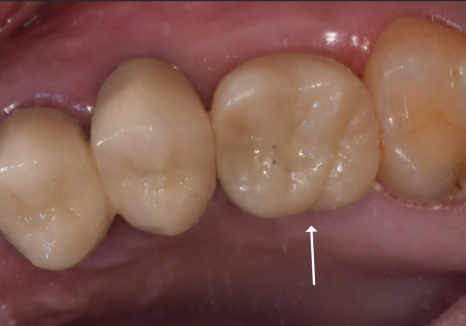

250409

덕분에 큰 문제없이

지르코니아 보철로 마무리가 잘 되었네요~

240527(전) 250409(후)